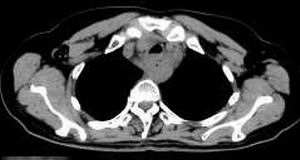

女,61岁,吞咽困难(包括开水)已久。

食道中上段癌并锁骨上窝淋巴结转移.

1、同意食道上段ca併淋巴结转移。

2、做食道呑钡就一目了然。

3、右侧甲状腺是否有问题?是否甲状腺ca转移食道上段。因为肿块顶部图像没有,请楼主展示,谢谢!

食道中上段中分化鳞癌伴锁骨上淋巴结转移

大家都很正确,谢谢!